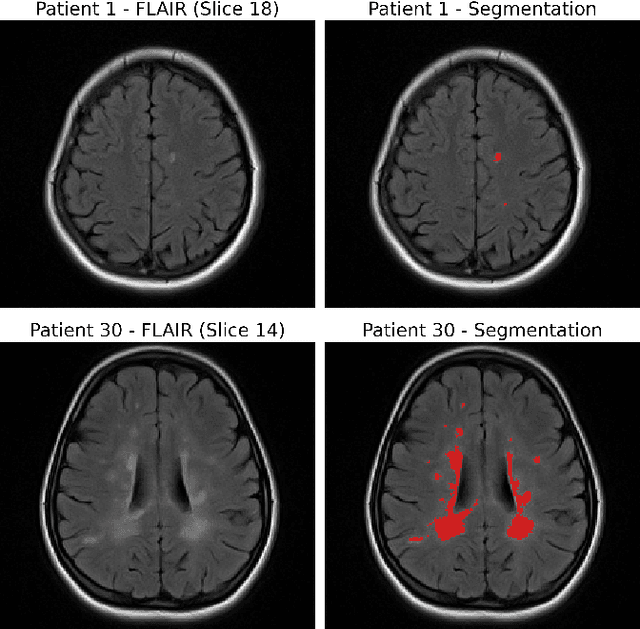

Abstract:Background: Accurate lesion segmentation is critical for multiple sclerosis (MS) diagnosis, yet current deep learning approaches face robustness challenges. Aim: This study improves MS lesion segmentation by combining data fusion and deep learning techniques. Materials and Methods: We suggested novel radiomic features (concentration rate and R\'enyi entropy) to characterize different MS lesion types and fused these with raw imaging data. The study integrated radiomic features with imaging data through a ResNeXt-UNet architecture and attention-augmented U-Net architecture. Our approach was evaluated on scans from 46 patients (1102 slices), comparing performance before and after data fusion. Results: The radiomics-enhanced ResNeXt-UNet demonstrated high segmentation accuracy, achieving significant improvements in precision and sensitivity over the MRI-only baseline and a Dice score of 0.774$\pm$0.05; p<0.001 according to Bonferroni-adjusted Wilcoxon signed-rank tests. The radiomics-enhanced attention-augmented U-Net model showed a greater model stability evidenced by reduced performance variability (SDD = 0.18 $\pm$ 0.09 vs. 0.21 $\pm$ 0.06; p=0.03) and smoother validation curves with radiomics integration. Conclusion: These results validate our hypothesis that fusing radiomics with raw imaging data boosts segmentation performance and stability in state-of-the-art models.